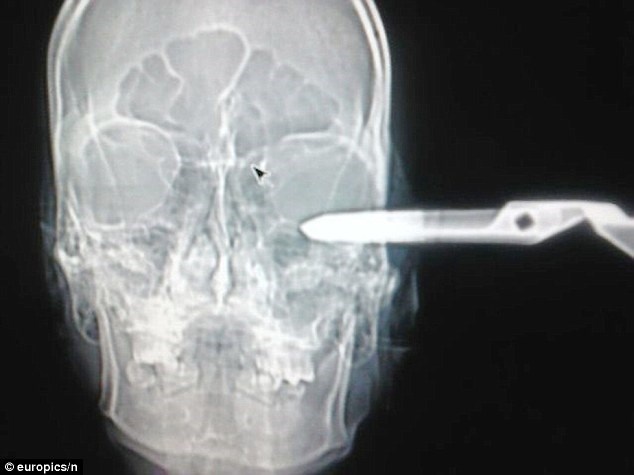

Hình chụp X-quang chiếc kéo đâm vào hộp sọ anh Jonas. Ban đầu, nhân viên và bác sĩ ở bệnh viện nghĩ rằng đây chỉ là trò đùa cho đến khi anh này ngất xỉu, các bác sĩ đã đưa anh này vào phòng cấp cứu khẩn cấp. Một phát ngôn viên của bệnh viện cho biết: "Bệnh nhân đã bị chiếc kéo đâm sâu vào hộp sọ bên trái, ngay trên đỉnh thùy não. Anh ấy quả thật rất may mắn khi có thể sống sót". |

Chiếc kéo đâm vào sâu vào đỉnh thùy não và thật may mắn là anh này đã sống sót. Các nhân chứng kể lại rằng khi Jonas đang ngồi cùng bạn trong quán bar thì bất ngờ bị một người đàn ông đến gây sự và tấn công. Tuy rất đau đớn nhưng anh vẫn bình tĩnh lên xe và cùng bạn đến bệnh viện. Các nhân viên ở đây đặt biệt danh cho Jonas là "Quý ông" nhờ cách cư xử lịch lãm ngay cả trong tình trạng nguy kịch. |